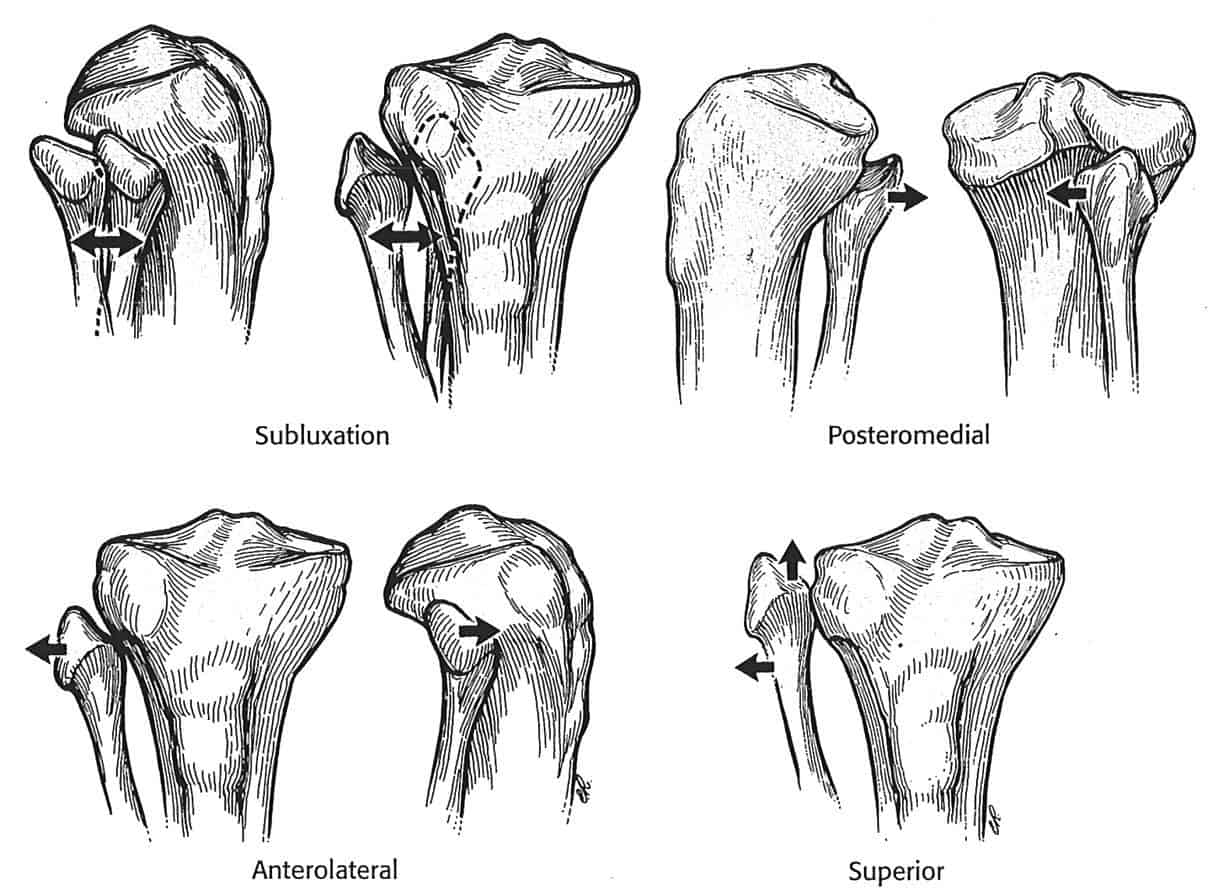

– Khớp gối là một khớp bản lề, lớn nhất cơ thể, nằm ngay dưới da, bao gồm đầu dưới xương đùi, đầu trên xương chầy và xương bánh chè. Các thành phần này được kết nối với nhau bởi hệ thống các dây chằng, bao khớp, trong đó quan trọng nhất là dây chằng chéo trước và dây chằng chéo sau. Hai dây chằng này giữ cho đầu trên xương chầy và đầu dưới xương đùi không bị trượt theo chiều trước sau khi khớp gối vận động.

– Ngoài ra hệ thống dây chằng bên trong và dây chằng bên ngoài giữ cho gối không bị trượt sang bên. Lót giữa lồi cầu đùi (hình cầu) và mâm chầy (phẳng) là sụn chêm trong và sụn chêm ngoài, làm gia tăng diện tiếp xúc, phân bố đều lực tác động lên gối.